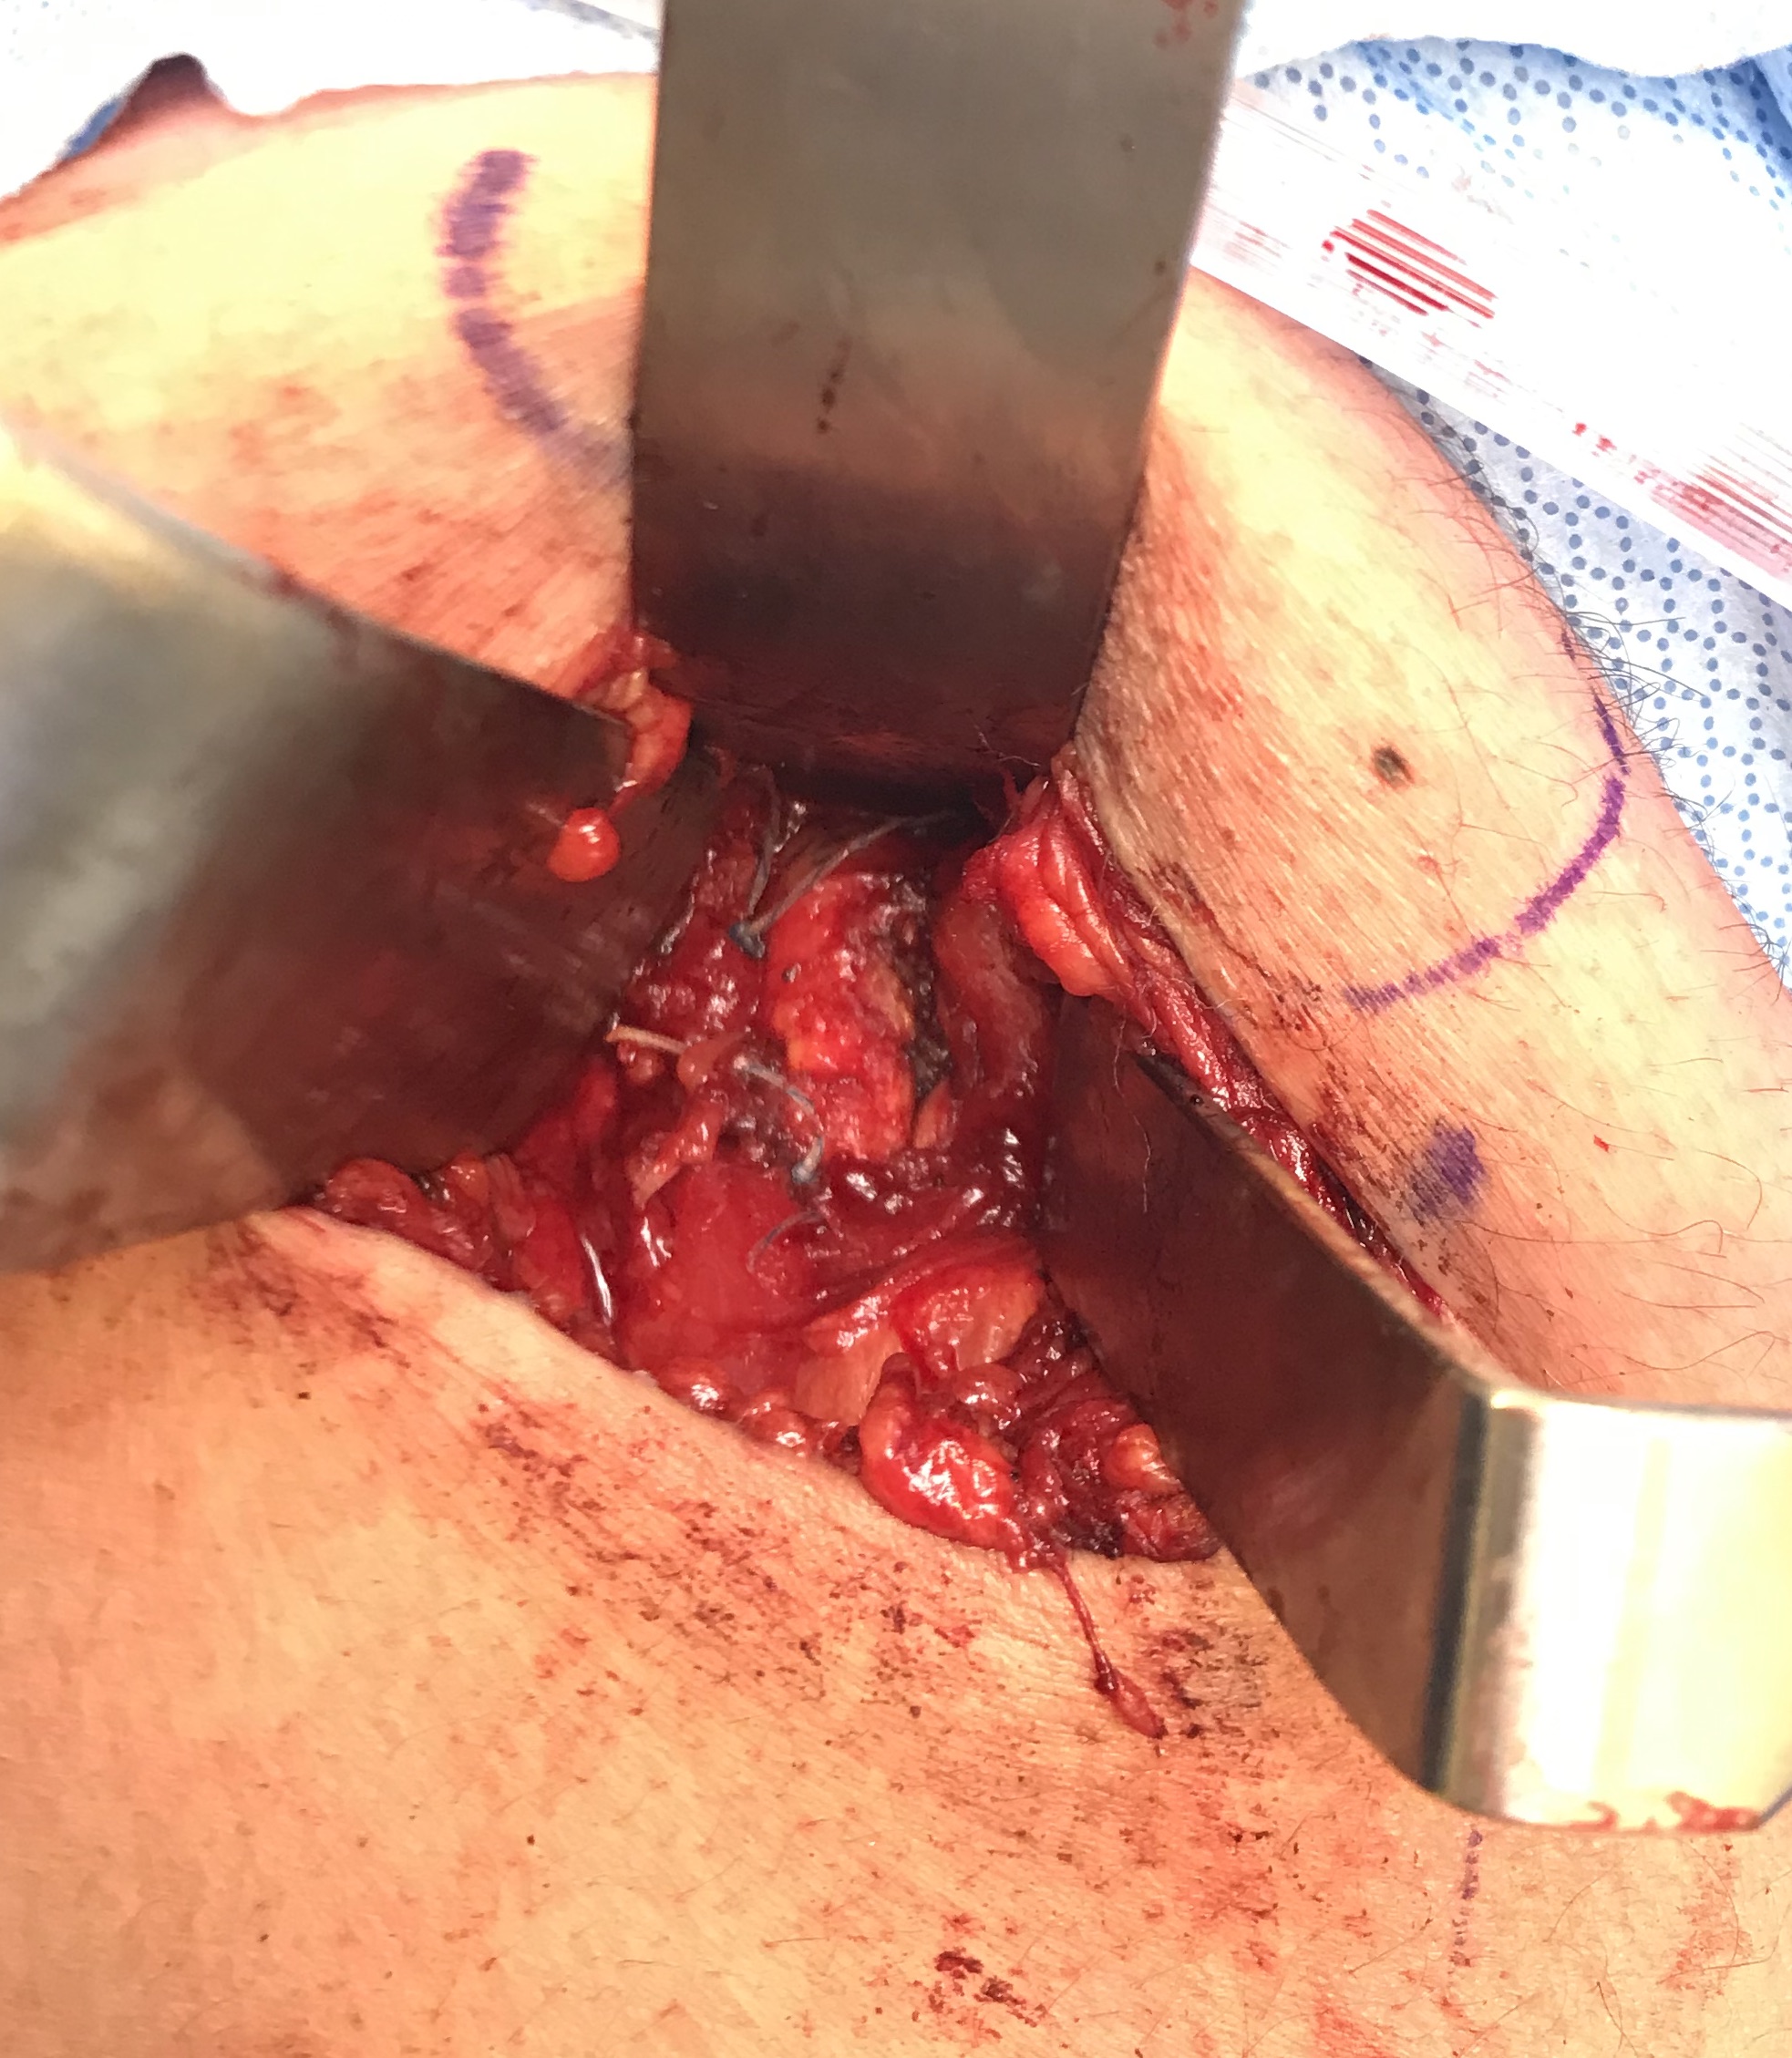

Post suture anchor repair

Identify sciatic nerve lateral and semimembranosus tendon medial to conjoint muscle belly and tendon

Divide semimembranosus tendon and suture to conjoint tendon (star - sciatic nerve, # - conjoint tendon)